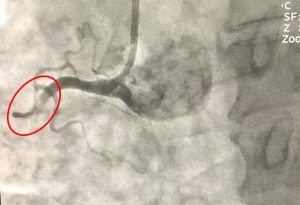

Bệnh viện Đa khoa Xuyên Á – Vĩnh Long (BVXA – VL) đã tiến hành phẫu thuật tạo hình thân sống bằng phương pháp bơm cement sinh học điều trị thành công cho hai bệnh nhân lớn tuổi bị xẹp đốt sống do loãng xương.